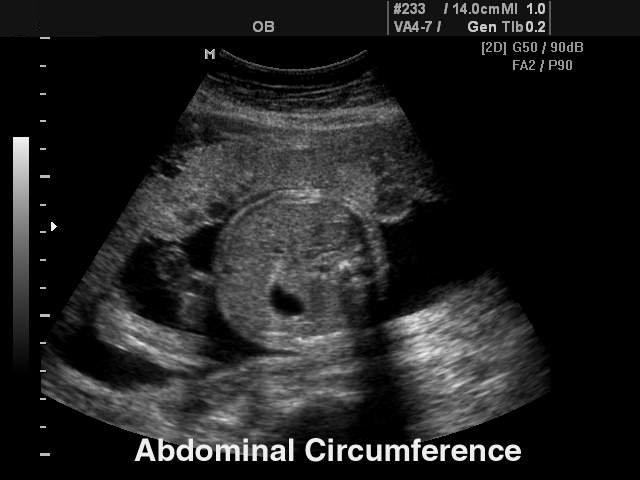

- Пакет акушерских исследований: биометрия плода, краниологическое исследование плода, исследование длинных костей плода, измерение индекса околоплодных вод (AFI), допплер плода и др.

- Биометрия плода включает измерения теменно-копчиковой длинны (CRL), размера плодного пузыря (GS), бипариетальный размера головки плода (BPD), затылочно-лобного расстояния (OFD), длины окружности головы плода (НC), передне-заднего размера брюшной полости (APD), поперечного размера брюшной полости (TAD), окружности живота (AC), площади сечения тела (FTA), длины бедра (FL), поперечного (TTD) и передне-заднего (APTD) размеров тела плода.